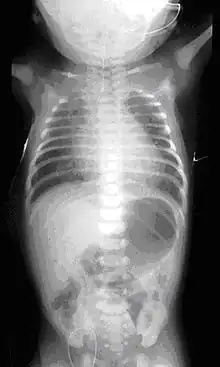

Plain X-ray of the chest and abdomen showing a feeding tube unable to move beyond an upper esophageal pouch.

On plain X-ray, a feeding tube will not be seen pass through the esophagus and remain coiled in the upper oesophageal pouch.[8]